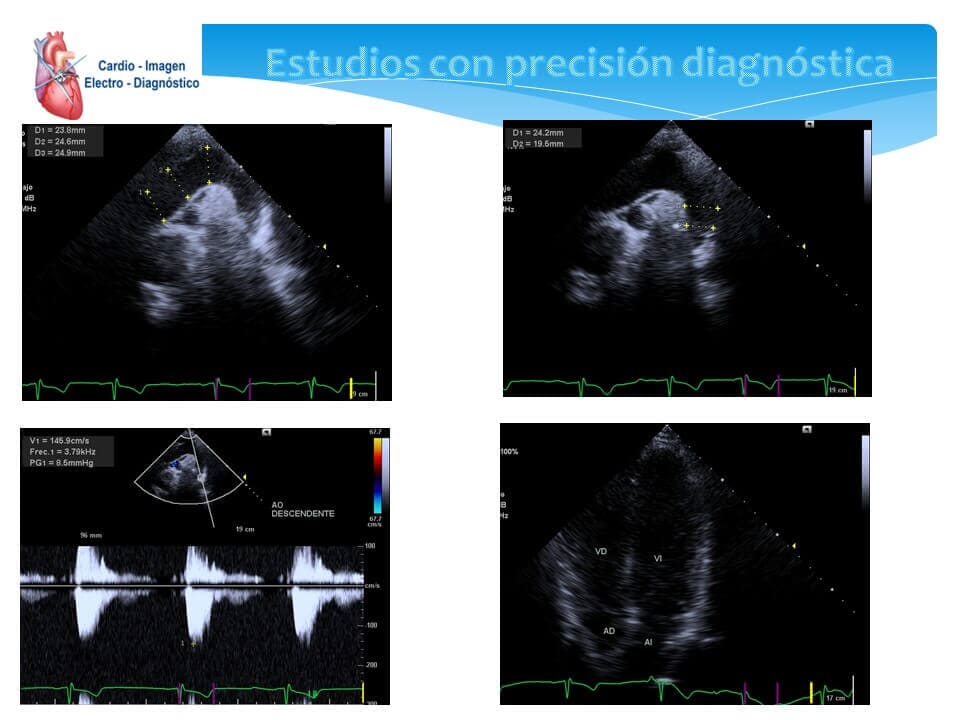

- Ecocardiograma transtorácico

- Ecocardiograma Doppler

- Ecocardiograma bidimensional

- Ecocardiografía